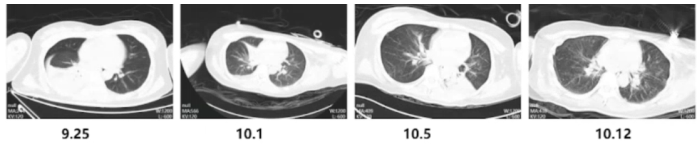

(5)康复措施及效果:复查影像学可见患者肺部炎性病变较前减少。

图片